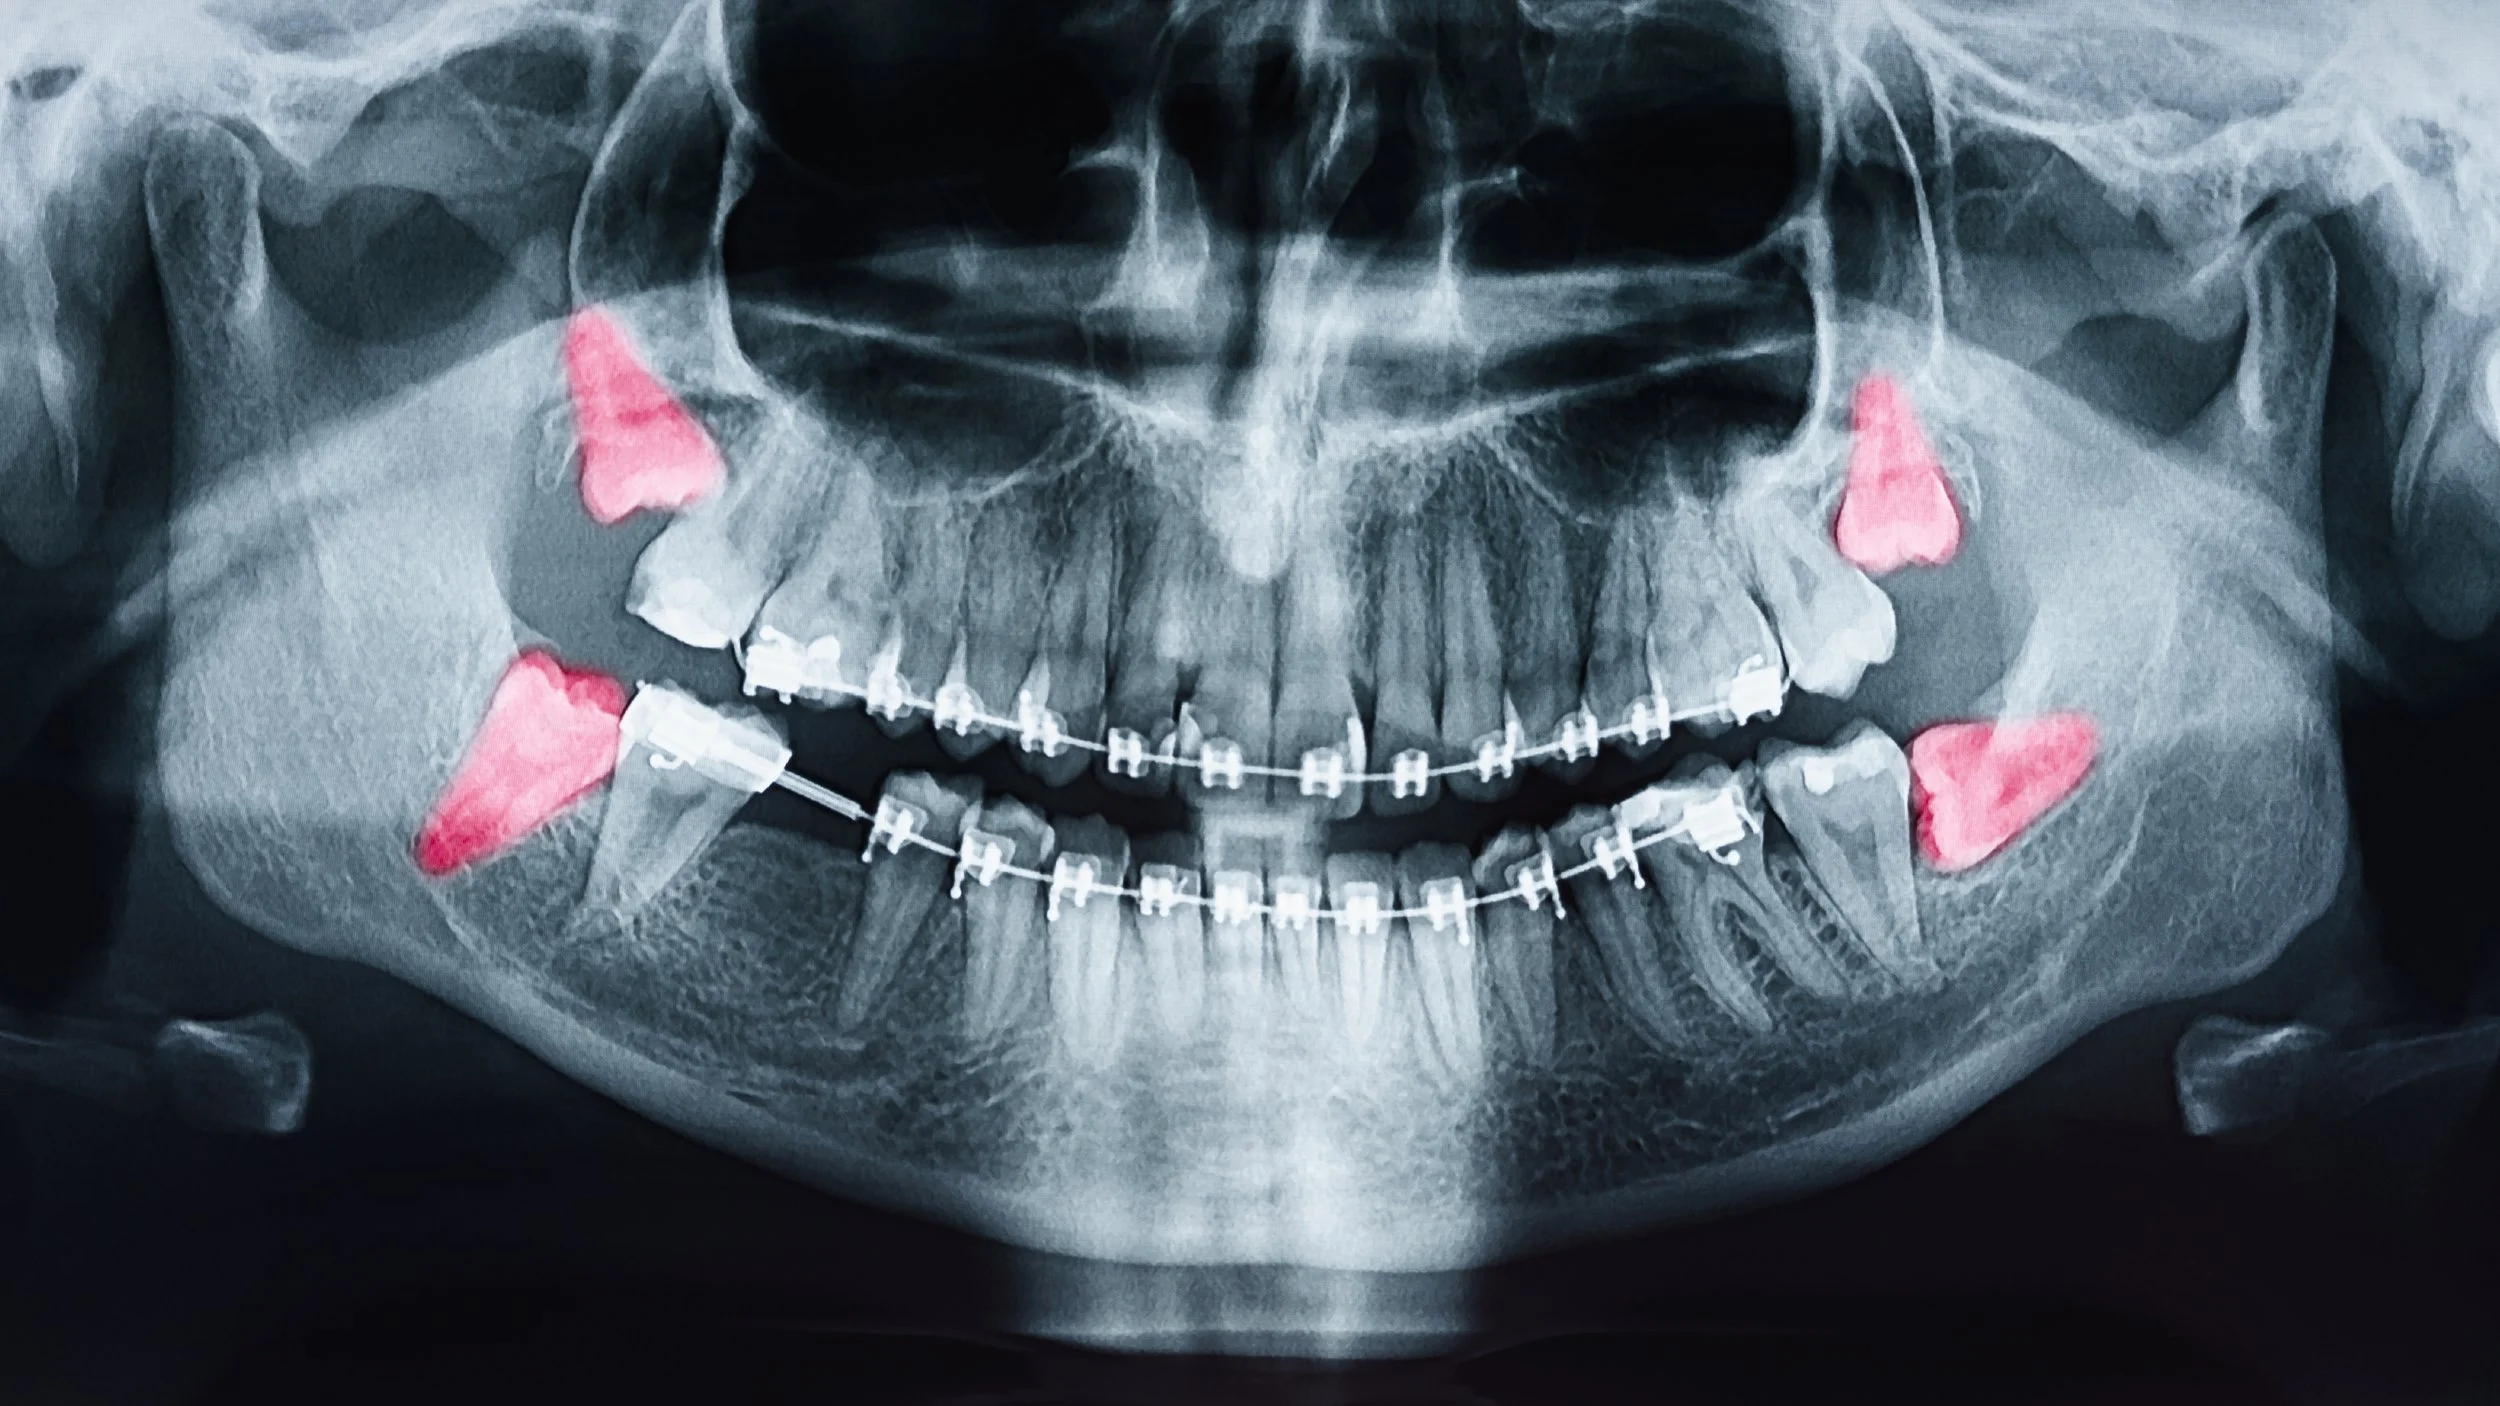

Although wisdom teeth are commonly removed, not all wisdom teeth need to be taken out. Extraction is only necessary if they are causing, or are likely to cause, oral health problems. Using X-rays and routine exams, dentists can monitor wisdom teeth, evaluate their position, and determine whether removal is the best option.

• Impaction: Wisdom teeth that are trapped under the gum or jawbone can cause pain, swelling, or infection.

• Cysts: In some cases, wisdom teeth can develop cysts that damage the surrounding bone and tooth roots.